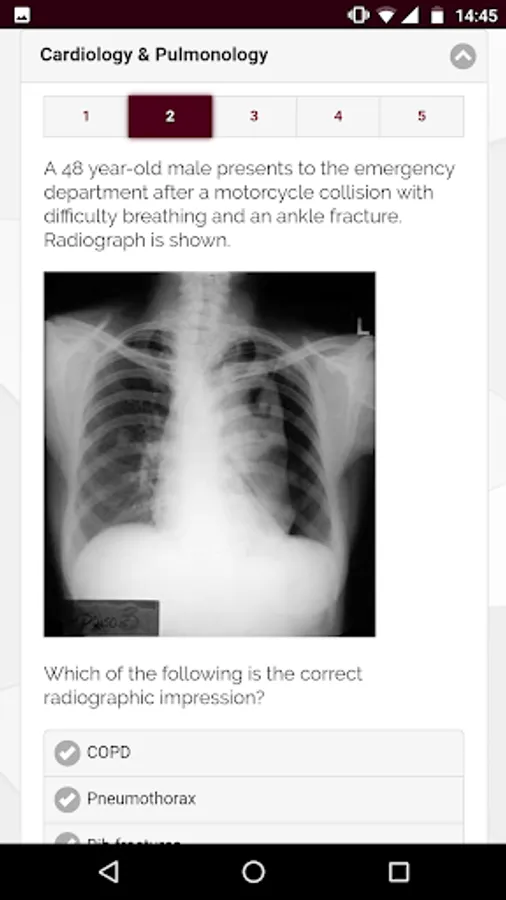

The ABPM App accompanies the website www.abpmed.org. It features information about ABPM and examinations, examination practice questions, reference ranges, biomechanical examination templates, a body mass index (BMI) calculator, a weight conversion calculator, and can receive optional notifications regarding news and events.